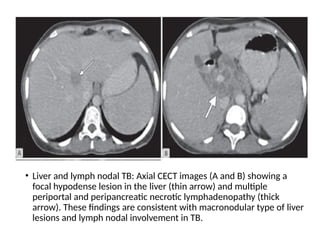

• Liver and lymph nodal TB: Axial CECT images (A and B) showing a

focal hypodense lesion in the liver (thin arrow) and multiple

periportal and peripancreatic necrotic lymphadenopathy (thick

arrow). These findings are consistent with macronodular type of liver

lesions and lymph nodal involvement in TB.